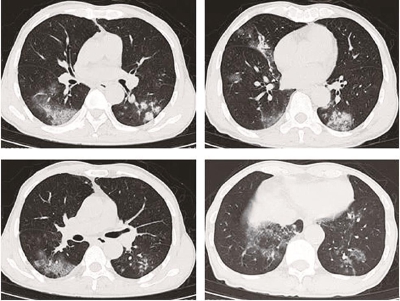

68岁患者王先生近日因“发热、咳嗽、气短10日”入院。入院前十天,他出现畏寒、发热,恶心,咳嗽,体温最高达39.0℃,他口服克感敏后,体温下降,但咳嗽、咳痰加重,接着他使用莫西沙星静滴数天,症状也无好转,之后他进行胸部CT片,发现双肺斑片影。于是拟诊“肺炎”收入我院。

医生仔细追问病史,原来他之前曾接触废旧机械厂废料,废料成分为不明的金属及晶体。在处理废料5个多小时都未佩戴防护口罩等,他当时即感咽痒、咳嗽,第二天出现全身乏力发热等症状,他自认为“感冒”,未予重视,后症状逐渐加重才进行就诊。结合此病史及影像学等资料,呼吸中心医生诊断过敏性肺炎,予以相应的治疗症状胸部CT好转后出院。